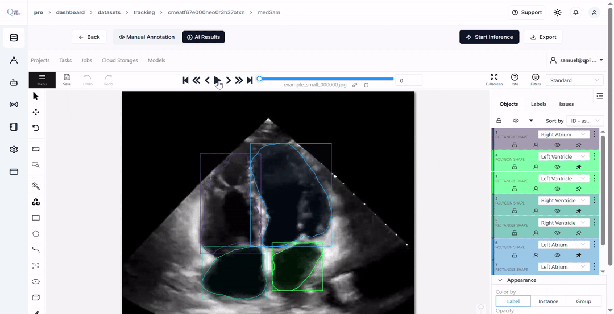

Review Annotated Frames

Once inference is complete, you will be redirected to a page showing the generated annotations for all frames.

-

Carefully review the annotations and make any necessary refinements for accuracy.

Export the Annotations

- On the review page, click the âExportâ button.

- Confirm the export action.

- The annotated dataset will be downloaded to your system for further use.